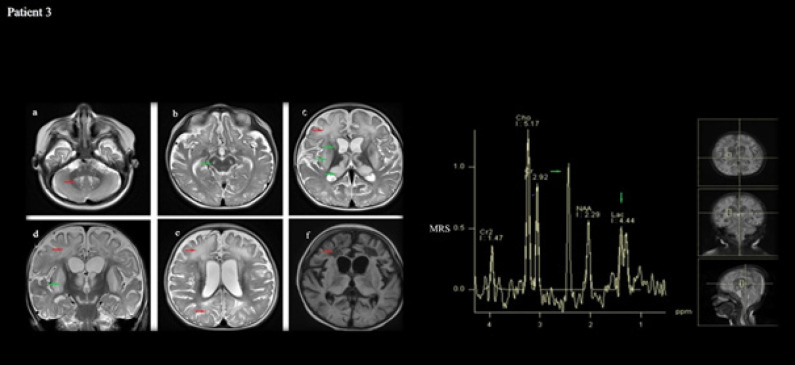

The Succinate Dehydrogenase (SDH) enzyme is known as Complex-II in the electron transport chain. This study reports the clinical and molecular investigations of three pediatric patients (two of whom are siblings), with histochemical and biochemical evidence of a severe, isolated complex II deficiency due to SDH gene mutations. The patients presented with severe hypotonia, developmental delay, spasticity, macrocephaly, and megalencephaly. Magnetic Resonance Imaging (MRI) revealed signal changes in the frontal, temporal, parietal, occipital cerebral, and cerebellar white matter, corpus striatum, thalamus, substantia nigra, inferior olivary nucleus, pyramidal tracts at the level of the pons and posterior limb of the internal capsule. Other typical findings involved a high succinate peak at 2.42 ppm and lactate peak at 1.3 ppm in Magnetic Resonance Spectroscopy (MRS). The siblings presented due to compound heterozygous c.143A>T (p. Asp48Val) and c.308T>C (p. Met103Thr) SDHB mutations, while the other patient presented due to compound heterozygous c.1754G>A (p. Arg585Gln) and c.1786G>C (p. Asp596His) SDHA mutation. The demonstration of succinate peak, particularly MRS, is highly diagnostic regarding SDH deficiency. MRS should be a standard part of routine radiological exams when there is a suspicion of a neurometabolic disease, especially mitochondrial disorders. Additionally, employing Next-Generation Sequencing (NGS) is advisable for patients as it allows for accurate diagnosis without requiring invasive procedures like muscle biopsies.